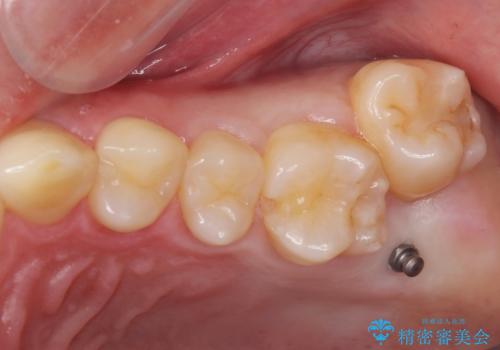

左上の奥歯がシザーバイトがありワイヤーで部分的な矯正を行い、シザーバイトを改善した後にインビザラインで全体的な矯正治療を行いました。

シザーバイトは歯と歯が噛み合っていないのでしっかり噛むように処置をする必要があります。